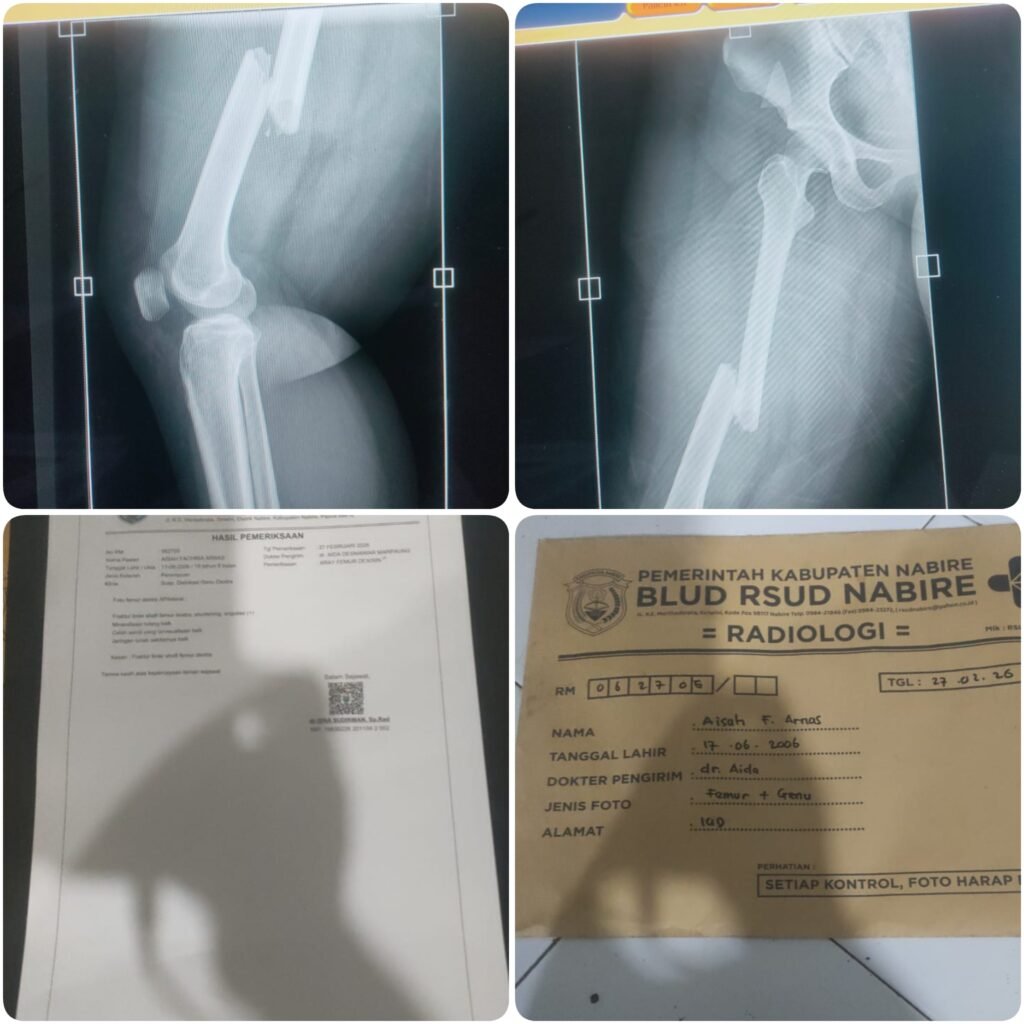

Newshunterinvestigasi.web.id | Nabire, Papua Tengah – Ruas Jalan Poros Samabusa (Waharia), Kabupaten , kembali memakan korban. Seorang mahasiswi, Aisya Fahri Anas, harus dilarikan ke rumah sakit setelah mengalami patah tulang paha akibat terjatuh diduga karena menghantam jalan berlubang, Jumat (27/2/2026).

Korban diketahui tengah dalam perjalanan pulang ketika sepeda motor yang dikendarainya kehilangan keseimbangan usai melewati lubang di badan jalan. Warga yang membantu evakuasi menyebut kondisi jalan memang “seperti jebakan” bagi pengendara, khususnya pada malam hari atau saat hujan deras.

Peristiwa yang menimpa Aisya Fahri Anas menjadi alarm keras bahwa lubang di Jalan Poros Samabusa bukan sekadar kerusakan fisik, melainkan potensi ancaman nyata terhadap nyawa warga.